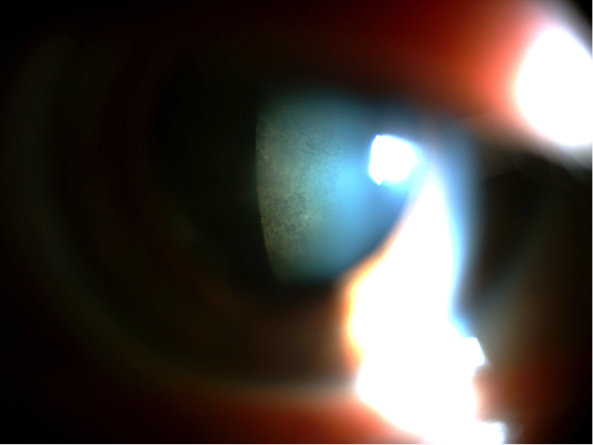

La queratoconjuntivitis epidémica es la forma más agresiva, suele ser bilateral y comienza entre 7 y 10 días tras el contacto (y el paciente puede ser contagioso durante los 10 a 14 días siguientes al inicio de los síntomas). Suele presentar reacción folicular en la conjuntiva, con petequias y en ocasiones hemorragias. La queratitis punteada epitelial es frecuente, muy molesta y en ocasiones dolorosa, pudiendo aparecer erosiones epiteliales grandes. La adenopatía preaucircular puede ser prominente, y entre la primera y segunda semana pueden presentarse infiltrados subepiteliales, debido a la reacción inmune provocada por el virus, causando fotofobia y mala visión que pueden persistir durante semanas.

Queratitis punteada epitelial